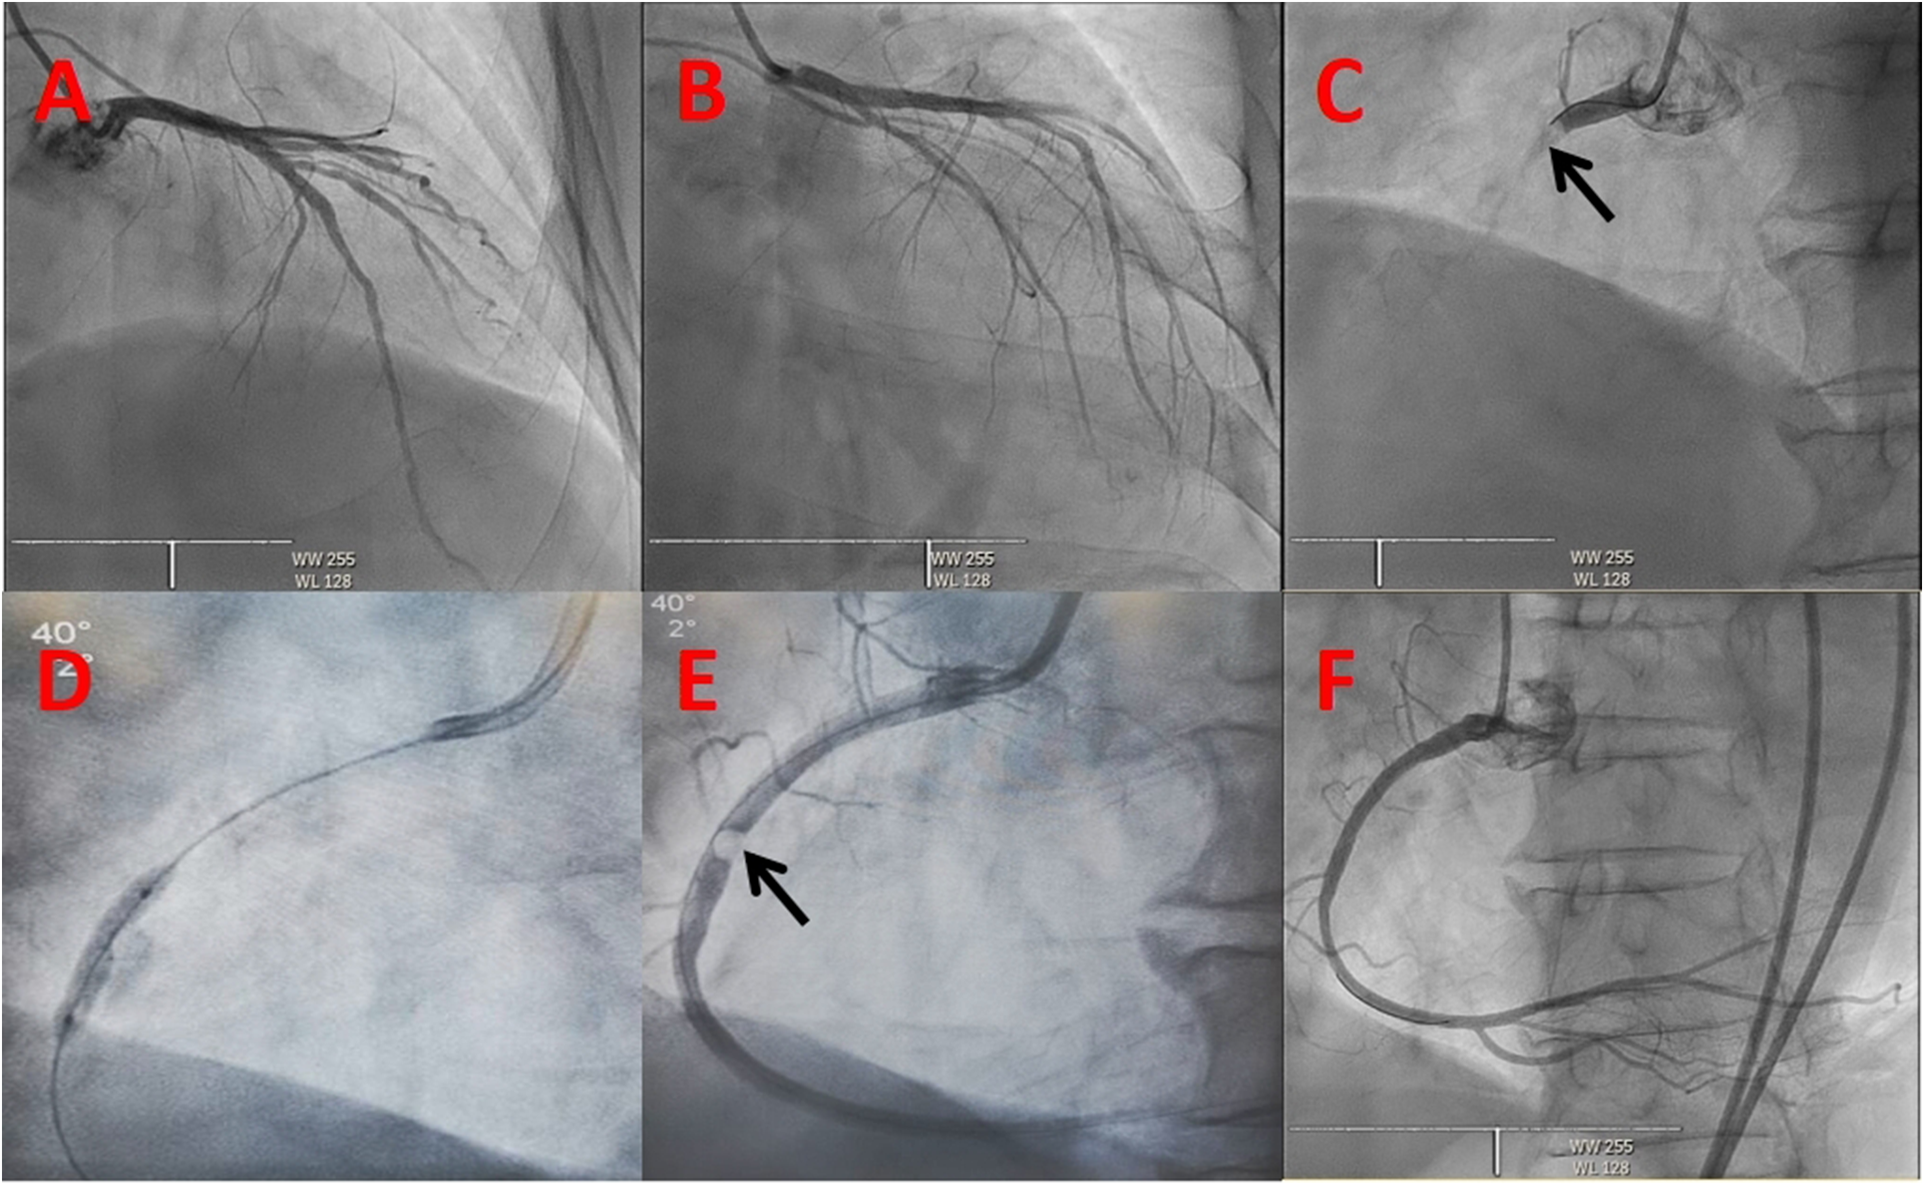

Figure 2

Coronary angiogram. The initial view of the coronary angiogram in (A–C) revealing a normal left coronary system and an embolism in the proximal right coronary artery (dark arrow): (A) Cranial 30, (B) RAO 30 + Caudal 30, (C) LAO 40. (D) Hourglass sign of balloon angioplasty. (E) Embolus in the proximal right coronary artery (dark arrow). (F) Right coronary angiogram showing TIMI 3 blood flow after the intervention.

Unfractionated heparin was given by loading 6,000 IU intravenously and infusing with 1,000 IU per hour during the procedure to maintain the activated coagulation time greater than 300 s. An emergency coronary angiogram showed a total occlusion of the proximal right coronary artery (RCA) with a globular filling defect without any collateral vessels from the left coronary system (Figure 2). A 6 Fr JR 4.0 guiding catheter (Teruma, Japan) was engaged in the RCA. Run-through wire (Teruma, Japan) and Sion wire (ASAHI, Japan) failed to pass through the lesion. We considered that the occlusion was not a common thrombotic lesion and attempted to open the lesion using Fielder XT (Abbott, USA) wire under the Finecross microcatheter (Teruma, Japan). With careful manipulation, the wire was advanced to the distal end of the RCA through the occlusion. A 1.5 × 15 mm Maverick balloon (Boston Scientific, USA) was successfully passed through the lesion and was inflated to 6 atm, but the coronary angiogram showed no blood flow in the RCA. The balloon was converted to a 2.0 × 20 mm Maverick balloon and inflated to 6 atm, but again, it did not yield the desired results. We then performed aspiration thrombectomy using Rebirth (Goodman, Japan). But no thrombus was aspirated. Then, we used a Sprinter balloon of different sizes (2.0 × 20 mm and 2.5 × 15 mm) (Medtronic, USA), which successively dilated the lesion, and an hourglass sign was revealed (Figure 2). The blood flow recovered to TIMI 1 and the embolus ran deeper into the RCA (Figure 2). To make the characteristics of the embolus clear, we decided to perform intravenous ultrasound (IVUS) (Boston Scientific, USA). IVUS showed calcification and posterior echo attenuation in the mid-RCA (Figure 3). We realized that the embolus was hard and calcified, and the usual methods would not work. The option of emergency coronary artery bypass grafting was considered. But the patient's hemodynamics were still unstable, and he suffered ventricular fibrillation several times during the procedure. The cardiac surgeon reasoned that the mobility of the embolus in the RCA rendered it difficult to be detected accurately and that the surgical risk was too high. The patient's family also did not favor surgery. After a detailed discussion, we decided to use a balloon-based technique to extract the embolus from the coronary artery. First, we would use a balloon to pass through the embolus to the distal portion of the RCA. Second, the balloon would be inflated to low pressure and then be pulled backward to bring the embolus together out of the coronary artery. Finally, we would perform selective organ angiography to locate the escaped culprit embolus and prevent embolization to the major related organs, i.e., brain, intestines, and kidneys.